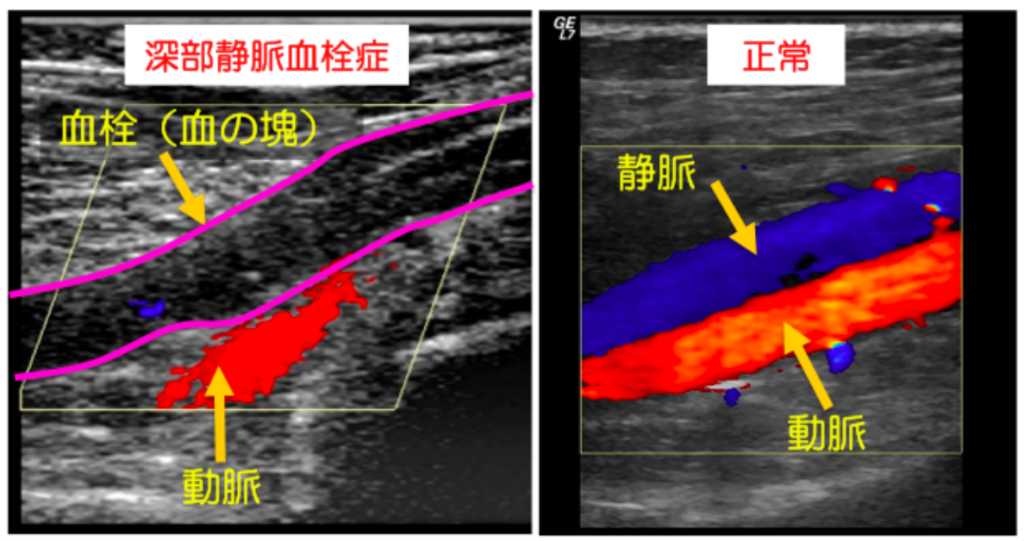

ただし、血栓が溶解しない場合や、損傷がなくても血栓が形成される場合があります。これらの血栓は、心臓発作や脳卒中などの危険な合併症を引き起こす可能性があります。血栓の種類が異なれば、症状も異なります。最も一般的なタイプの血栓は深部静脈血栓症 (DVT)です。

• 深部静脈血栓症 (DVT): DVT は通常、人の大腿部、骨盤、下肢、場合によっては腕に形成されます。 DVT は静脈を通る血流を部分的または完全に遮断し、手足に損傷を与える可能性があります。